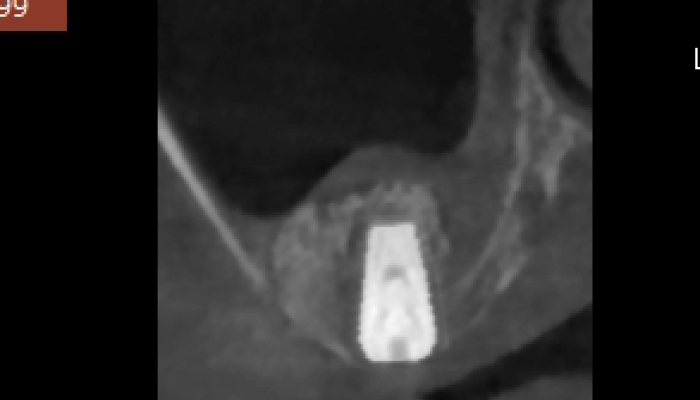

임플란트 수술시, 상악동과 잇몸뼈 사이에 뼈가 남아 있지 않았을 때 상악동막을 들어올리고 빈 공간에 뼈를 이식하여 임플란트 식립을 위한 공간을 확보하는 수술을 상악동 거상술이라 합니다.

밀도가 높고 두꺼운 턱뼈가 구성된 아래턱과는 달리 위턱은 얇은 뼈 위에 코와 광대 사이 빈 공간에 식립해야 하는 고난도 수술로 임플란트 수술 경험이 많은 의료진에게 받는 것이 중요합니다.

상악동거상술 시술과정

상악동거상술은 고난도 수술로 임플란트 수술 경험이 많은 의료진에게 받는 것이 중요합니다.

뼈이식 / 임플란트 식립공간 확보

잇몸을 절개하고 난 후 뼈를 넣고 상악동을 들어 올릴만한 작은 통로를 만들어 뼈이식할 공간과 임플란트 식립할 공간을 확보합니다.

잇몸 뼈이식 시술 진행

들어올린 빈 공간에 뼈를 이식하는데 이때 사용되는 뼈이식 재로로는 자가치아뼈, 자가골, 인공뼈, 합성골 등이 있습니다.

임플란트 매식체 식립

잔존하고 있는 잇몸뼈의 양에 따라 뼈이식과 동시에 임플란트 식립하기도 하고 6-9개월 후 식립하기도 합니다.

상악동거상술 수술사진